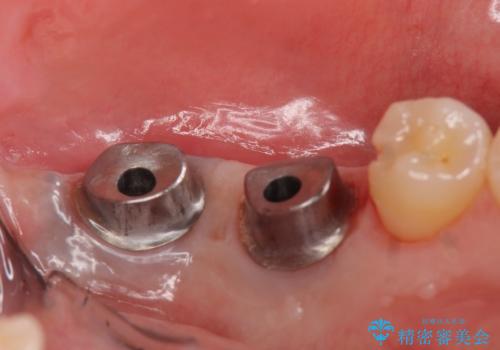

左下にインプラント(ストローマン)を2本埋入し、オールセラミッククラウンによる補綴を行いました。

当院では主にストローマンという種類のインプラントを治療に用いています。

ストローマンは世界的にもNo1のシェアを誇り、骨との適合にも優れたインプラントです。

カスタムアバットメントは患者様それぞれの歯茎に合わせて製作されたオーダーメイドのアバットメントです。

既製のアバットメントに比べ適合がよく、高い清掃性を誇ります。